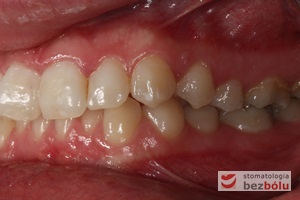

Pacjentka lat 22 zgłosiła się do naszej placówki celem podjęcia leczenia ortodontycznego. Głównym oczekiwaniem pacjentki była poprawa estetyki uśmiechu oraz brak ekstrakcji zębów na drodze do jej uzyskania. Ze względu na liczne stłoczenia zębów w górnym i dolnym łuku, dość duży materiał zębowy w porównaniu z bazą kostną, a także zgryz przewieszony boczny prawostronny po dokładnej analizie cefalometrycznej oraz analizie modeli diagnostycznych zastosowano leczenie bezekstrakcyjne z wykorzystaniem strippingu jako alternatywy dla usuwania zębów, mającego na celu uzyskanie miejsca w łuku na uszeregowanie zębów. Po fazie aktywnego leczenia trwającego 18 miesięcy zastosowano leczenie retencyjne w postaci szyny retencyjnej w łuku górnym oraz retainera stałego w łuku zębowym dolnym klejonego od kła do kła.